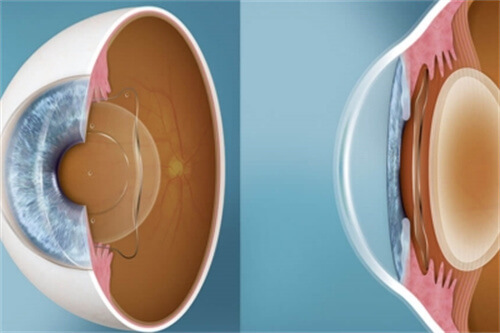

然而,关于ICL植入后,特别是其关键指标之一——拱高(即晶体与晶状体前囊膜之间的空间距离)是否会随时间发生变化,一直是患者关心的焦点。

拱高作为评估ICL植入结果的重要指标之一,直接关系到术后的视觉质量、晶体稳定性及眼内健康。适宜的拱高范围既能确保视力清晰,又能减少并发症的风险,如晶体旋转、前房变浅或继发性青光眼等。

在ICL植入初期,由于眼内组织对异物的适应性反应,以及晶体与周围组织的相互作用,拱高确实可能经历一定程度的微小变化。这种变化多属于生理性调整,一般在术后数周至数月内趋于稳定。

大量临床研究和长期随访数据显示,一旦眼内组织适应了ICL的存在,拱高将维持在一个相对稳定的范围内。尽管个体间存在差异,但多数患者的拱高在术后一年左右即达到稳定状态,且此后的变化微乎其微。